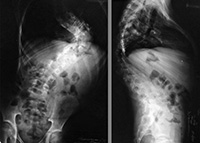

Софии 11 лет, она из поселка Воротынск Бабынинского района Калужской области. Диагноз – левосторонний кифосколиоз грудопоясничного отдела позвоночника 4 степени, левосторонний реберный горб на фоне нейрофиброматоза. Впервые сколиоз выявлен в 2013 году и девочка получила инвалидность. Прогрессирование деформации достигло почти 90 градусов, усилились боли в спине и головные боли. Устранить искривление поможет операция коррекции деформации позвоночника современной металлоконструкцией производства Medtronic (США). Оплата имплантатов за счет бюджетных средств не производится. Стоимость базовой комплектации имплантатов и расходных материалов составляет 706 480 рублей.

Когда Софии исполнилось три года, бабушка – Любовь Николаевна, стала замечать, что внучка сутулится. Делать снимки боялись, не хотели лишний раз облучать ребенка рентгеном. Спохватились поздно, к 5 годам у нее диагностировали уже II степень сколиоза. Начали регулярное физиолечение в Калужской областной клинической детской больнице в Анненках.

Часто простужается. Боли в спине тоже постоянно беспокоят, София часто жалуется своей бабушке. Сколиоз развивается стремительно. Большую часть времени она лежит, горб уже более 90 градусов. Прогулка длится недолго, отойдет от дома на 20-30 метров и все, ей надо посидеть или полежать.